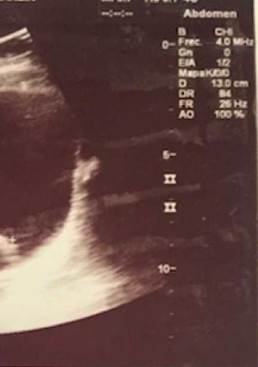

A pesar de la suspensión de CYC, luego de 8 meses, continúan los episodios recurrentes de hematuria, uno de ellos severo, que compromete el estado hemodinámico de la paciente, con disminución de hemoglobina hasta 7 g/dl y presencia de un gran coágulo intravesical (fig. 1). Se ampliaron los estudios por Nefrología y Urología pediátrica para otras causas de hematuria persistente, entre ellos polioma-virus, adenovirus, micobacterias, nefritis intersticial, cistitis eosinofílica, etc., los cuales fueron negativos. La uro-TAC documentó engrosamiento leve y difuso de las paredes de la vejiga; teniendo el estudio negativo para infección y persistencia de la sintomatología, se decidió realizar una cistoscopia, en la que se observó una mucosa hiperémica con vasculitis generalizada de la mucosa vesical.